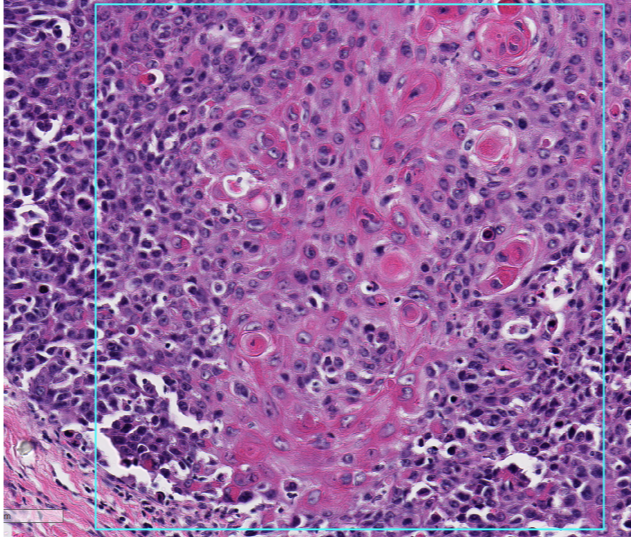

Q

This is from the eyelid and ocular bone, provide a histologic morphologic diagnosis. (Note: there is metastasis to the lung)

A

ocular squamous cell carcinoma with local bone invasion and pulmonary metastasis

Which tissue layers are affected by the neoplasm?

Is the cell of origin a round cell, epithelial, or mesenchymal population?

epithelial - formation of cords, nests by cohesive groups of polygonal cells

This is from a feline larynx, is this benign or malignant and why?

malignant, the presence of neoplastic clusters within the blood vessels, severe stromal invasion, lack of differentiation, increased mitotic rate, cellular variability